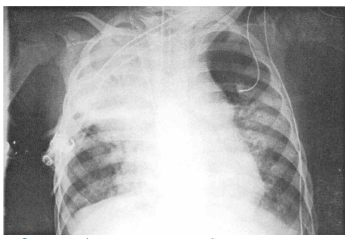

3 一位 8 歲男童因發燒一天住院,住院時之胸部 X 光如圖所示,白血球計數 13,500/mm3,白血球分類 band 6%, segment 81%, monocyte 4%, lymphocyte 9%, C-reactive protein 1.1 mg/dL。下列那一種感染的 可能性最高?

(A) Haemophilus influenzae type b (B) Streptococcus pneumoniae (C) Group A streptococcus (D) Staphylococcus aureus